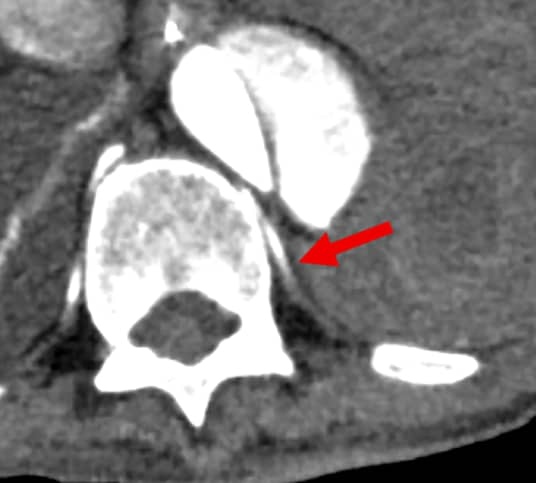

背景として、5年前に急性大動脈解離に対し全弓部置換術を施行されており、1か月前に人工血管感染のため開胸ドレナージおよび緊急予防的TEVARが施行されている。その1週間後、待機的に再全弓部置換術および大網充填が施行された。手術は問題なく終了したものの、術後9日に創部皮下の血腫を認めた。術後12日には胃管からの黒色排液や貧血の進行が認められ、上部消化管内視鏡検査が施行されたが活動性出血は指摘できず、出血源精査のため造影CT検査が施行された。左第11肋間動脈より活動性出血の所見があり、緊急的TAEを施行した。その後貧血の進行なく経過している。

今回の症例は、術後にある程度の日数が経過してから貧血の進行が顕在化していた。術直後から左胸水の増加が緩徐であったことや胃管から黒色排液を認めたことから、まず上部内視鏡検査が施行され、胸腔内の出血は積極的に疑われていなかった。実際、後方視的にも今回のCT以外では血胸を認めず、高頻度に撮影されていた胸部単純写真(臥位)では有意な変化は認められていなかった。そこで今回の撮像では胸部~骨盤部にかけて広範囲の活動性出血の検索が目的となっている。早期動脈相により動脈性の出血が同定でき、後期相の撮像により仮性動脈瘤等との鑑別も可能になっている。また、非造影検査により血性胸水の同定や石灰化と濃染域との鑑別も容易になっている。薄層やMPRの画像も作成されており責任血管の同定がしやすくなるとともに、治療(TAE)の一助にもなっている。